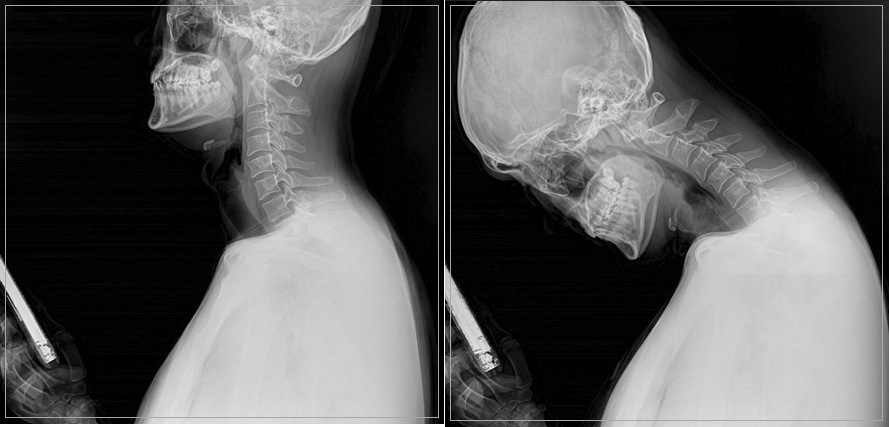

바른세상병원 척추센터 이근호(정형외과 전문의) 원장은 "장시간 구부정한 자세로 스마트폰이나 태블릿 등을 보는 자세가 습관이 되면 목에 통증을 유발할 수 있다. 바르지 못한 자세가 지속되면 C자로 있어야 할 목 뼈(경추)가 일자목이나 거북목으로 변형되어 통증을 일으키게 되고, 정상적인 'C자 커브'를 잃은 상태가 지속되면 디스크가 튀어나와 신경을 압박하는 목 디스크로 발전할 수 있다"며 "초기에는 뻐근함이나 피로감으로 느끼지만 시간이 지날수록 어깨와 팔이 아프고, 심한 경우 손이나 팔 저림 증상으로 이어질 수 있다"고 설명했다.

목 디스크를 예방하기 위해서는 무엇보다 바른 자세가 중요하다. 귀와 어깨선이 일치하도록 자세를 바로잡아 목뼈에 무리를 주지 않도록 해야 하고 스트레칭을 통해 근육과 관절, 인대의 긴장을 풀어주는 것이 좋다. 스마트폰을 이용할 때는 액정을 눈높이까지 올리고, 눈 사이의 거리를 30㎝ 이상 유지하면 목이나 어깨 통증뿐 아니라 눈의 피로도 감소시킬 수 있다. 수면 자세를 바로잡는 것도 중요하다. 특히 목 통증 환자의 경우 수면 시 가장 중요한 것은 경추를 받쳐주는 베개의 높이와 곡선인데, 뒷목 부분이 조금 높고 머리 중앙이 낮아 경추의 'C자 커브'를 유지할 수 있는 베개를 선택하는 것이 바람직하다.